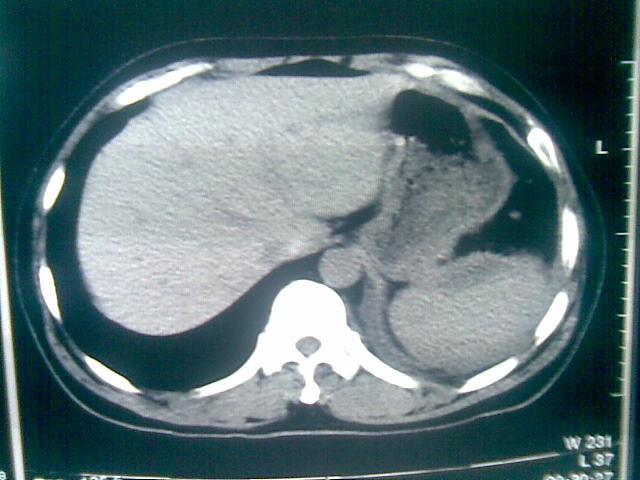

标题: CT23981:男,38岁阑尾炎术后透视胸腔积夜!做CT如下!积液包 [打印本页]

标题: CT23981:男,38岁阑尾炎术后透视胸腔积夜!做CT如下!积液包

可能与阑尾术后关系不太大,1.胸膜增厚粘连见少量气体。包裹脓气胸?左侧网膜囊脓肿?

.胸膜增厚粘连见少量气体。包裹脓气胸

左侧胸膜增厚、粘连+包裹液气胸。